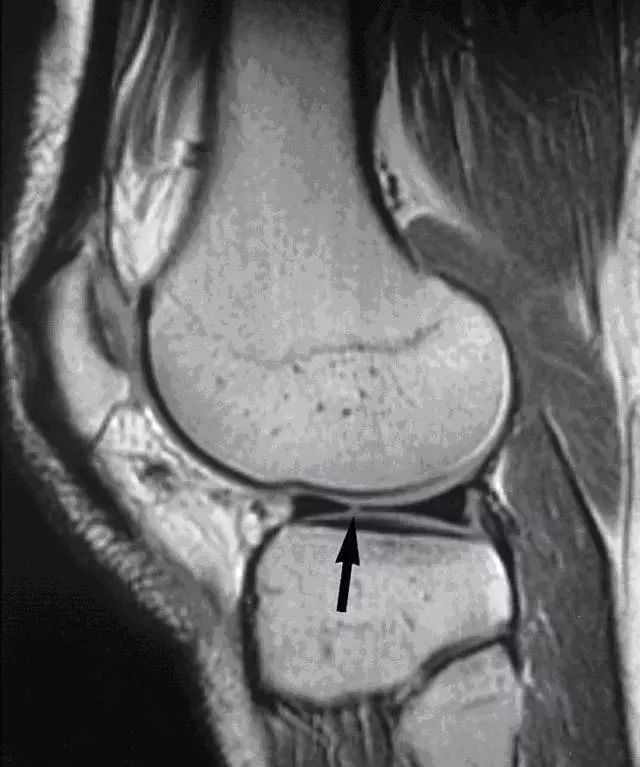

图 14 半月板根部撕裂和半月板膨出

左图:冠状面可见内侧半月板后角在与根部(与胫骨连接的部位,白色大箭头)交接的部位有一个全层的撕裂(白色小箭头),可与对侧正常结构对比(黑色箭头)。右图:冠状面可见内侧半月板体部膨出关节(白色箭头),半跨与胫骨平台上。本图还可看到内侧股骨髁的关节软骨有相较于外侧的退行性缺失。